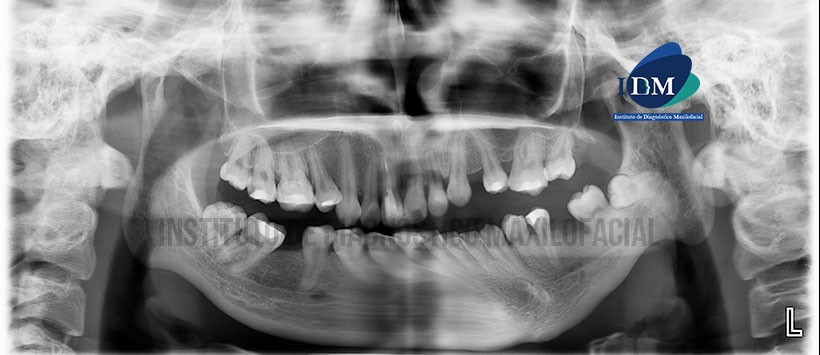

Paciente femenino de 28 años de edad, es referido al Instituto de Diagnóstico Maxilofacial (IDM) para evaluación tomográfica por presencia alteración en la ATM del lado izquierdo.

En la radiografía panorámica (Figura 1) se observa alteración en la morfología de las estructuras óseas de la articulación temporo-mandibular del lado izquierdo, caracterizado por pérdida severa de la dimensión vertical del cóndilo mandibular, aumento en el espesor del ancho condilar, ausencia de cuello condilar, erosión de superficie articular, elongamiento de la apófisis coronoide, pérdida de la escotadura sigmoidea aplanamiento de la cavidad glenoidea, aumento del espesor de la superficie articular del hueso temporal y acentuación de la escotadura antegenial del lado afectado.